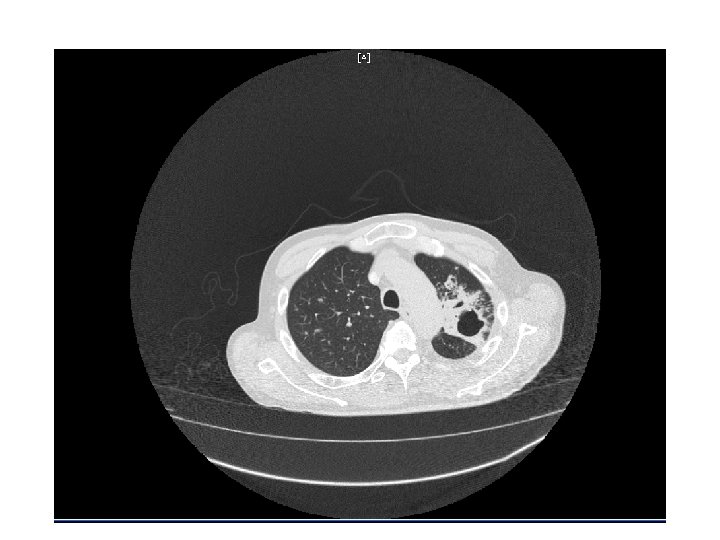

CT Chest • Multiple cavitary lesions • Largest left lung apex 3. 8 x 4. 7 cm with nodular thickened wall • Smaller cavitary lesions in L lung base • R lung: smaller areas of ground-glass opacities with areas of tree in bud appearance.

Chest radiography • Active disease: upper lobe infiltration/ cavity/ effusion • Healed: nodules, fibrotic scars, calcified granulomas or basal pleural effusion • Normal in latent TB • HIV: infiltrate in any lung zone, mediastinal or hilar LAD, normal